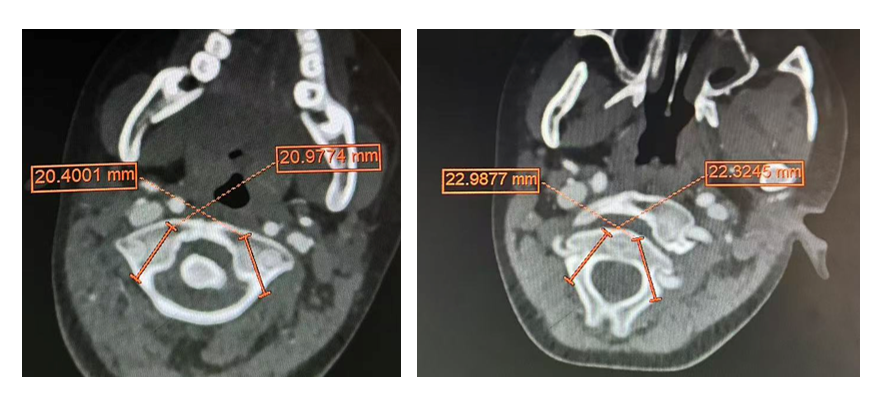

面对挑战,许正伟主任团队在西安市红会医院脊柱病医院院长闫亮、学科带头人贺宝荣主任带领下,为康康制定了周密的个性化方案。术前,三维椎动脉 CTA 精准「测绘」出脱位的详情与椎动脉的走向(图二及图三)。由于患儿无法配合常规牵引,团队决定在术中实施高难度的颅骨牵引复位。

手术日,在麻醉与神经电生理监测团队的全程护航下,主刀医生许正伟主任首先巧妙利用颅骨牵引,为完全脱位的关节实现了初步松解与部分复位。随后,在高端术中导航系统( S 8 )的实时引导下,将椎弓根螺钉精准、安全地置入寰椎与枢椎的微小椎弓根内。利用螺钉提供的稳固杠杆,脱位的关节被轻柔而坚定地「推」回了正常解剖位置,实现了完美复位。最后,取自患儿自身的髂骨块被植入后方,为永久性骨融合打下基础。